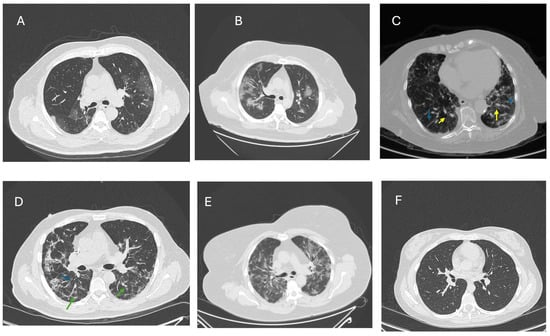

- Cha, M.J.; Solomon, J.J.; Lee, J.E.; Choi, H.; Chae, K.J.; Lee, K.S.; Lynch, D.A. Chronic Lung Injury after COVID-19 Pneumonia: Clinical, Radiologic, and Histopathologic Perspectives. Radiology 2024, 310, e231643. [Google Scholar] [CrossRef]

- Klos, K.; Jaskola-Polkowska, D.; Plewka-Barcik, K.; Rozynska, R.; Pietruszka-Waleka, E.; Zabicka, M.; Kania-Pudlo, M.; Maliborski, A.; Plicht, K.; Angielski, G.; et al. Pulmonary Function, Computed Tomography Lung Abnormalities, and Small Airway Disease after COVID-19: 3-, 6-, and 9-Month Follow-Up. J. Clin. Med. 2024, 13, 2733. [Google Scholar] [CrossRef]

- Babar, M.; Jamil, H.; Mehta, N.; Moutwakil, A.; Duong, T.Q. Short- and Long-Term Chest-CT Findings after Recovery from COVID-19: A Systematic Review and Meta-Analysis. Diagnostics 2024, 14, 621. [Google Scholar] [CrossRef]

- Watanabe, A.; So, M.; Iwagami, M.; Fukunaga, K.; Takagi, H.; Kabata, H.; Kuno, T. One-year follow-up CT findings in COVID-19 patients: A systematic review and meta-analysis. Respirology 2022, 27, 605–616. [Google Scholar] [CrossRef]

- Caruso, D.; Guido, G.; Zerunian, M.; Polidori, T.; Lucertini, E.; Pucciarelli, F.; Polici, M.; Rucci, C.; Bracci, B.; Nicolai, M.; et al. Post-Acute Sequelae of COVID-19 Pneumonia: Six-month Chest CT Follow-up. Radiology 2021, 301, E396–E405. [Google Scholar] [CrossRef]

- Han, X.; Fan, Y.; Alwalid, O.; Li, N.; Jia, X.; Yuan, M.; Li, Y.; Cao, Y.; Gu, J.; Wu, H.; et al. Six-month Follow-up Chest CT Findings after Severe COVID-19 Pneumonia. Radiology 2021, 299, E177–E186. [Google Scholar] [CrossRef] [PubMed]